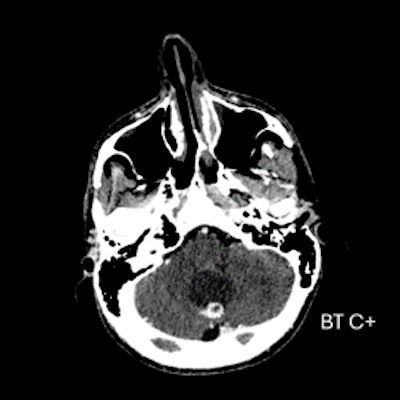

- A) Beyin BT incelemede; posterior fossada hipodens, düzgün sınırlı kistle beraber (oklar), posteriorunda 8 mm boyutunda, iyi sınırlı, kontrastsız BT’de parankim ile izodens, postkontrast görüntülerde yoğun kontrast tutulumu gösteren mural nodül komponenti (oklar) gözlenmektedir.